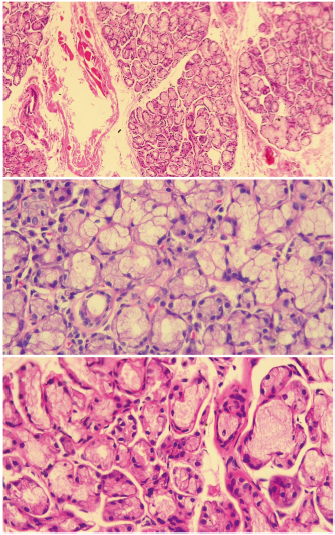

Del total de los pacientes con síntomas secos se encontró SLF en 8 (8,7%) de ellos (véanse figs. 1 y 2), según FS (el puntaje por focos se encontró entre 1 y 2 en 7 de los pacientes y en uno solo fue mayor de 2), mientras que 38 (41,30%) tuvieron biopsia positiva por CM (grados 3 y 4). Todos los pacientes que tuvieron positividad por medio del método de CM, pero que fueron negativos para SS cuando se utilizó la clasificación de FS, tuvieron sialoadenitis crónica no específica por medio de dicho método, excepto uno que presentó sialoadenitis crónica esclerosante. De acuerdo con los puntajes de los criterios ACR/EULAR (2016), se determinó la frecuencia de SS en 24 (26,09%) pacientes cuando se utilizó el método FS para BGSM (esta frecuencia incluyó a los 8 con positividad para SLF según FS) y en 32 (34,78%) pacientes cuando se utilizó el método CM; todos los casos se registraron en mujeres. Los 6 pacientes restantes con positividad para CM fueron clasificados como pacientes con síndrome seco, que si bien tenían positividad por medio de esta lectura en la BGSM, no tuvieron positividad en los demás criterios para SS. Con respecto a la edad, la mayor frecuencia de SS fue entre los 41 y los 65 años para los dos métodos histopatológicos (FS: 83,3%; CM: 78,3%).

Figura 1 Histología de glándula salival menor normal. En los tres cortes se observa glándula salival de histología normal de un paciente incluido en el estudio, en los que se ven acinos mucinosos con células mioepiteliales y ductos. La imagen superior en aumento de 10 x y las imágenes inferiores en aumento de 40 x. Fuente: elaboración propia.